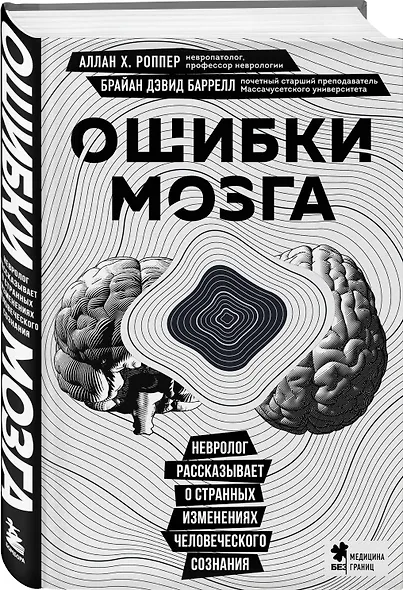

Х. Роппер Аллан, Баррелл Брайан Дэвид: Ошибки мозга. Невролог рассказывает о странных изменениях человеческого сознания

Книга клинического невролога Аллана Х. Роппера, написанная в соавторстве с Брайаном Дэвидом Баррелом, описывает самые интересные случаи из многолетней врачебной практики. Что такое дезориентация и психоз? Почему человек вдруг перестает испытывать эмоции? Из-за чего возникают нарушения памяти и речи, эпилепсия и инсульт? Почему так важно за симптомами увидеть личность пациента?

Вы узнаете, какие невероятные расстройства поражают мозг и какие медицинские головоломки порой преподносит неврология.

- Аллан Х. Роппер, Брайан Дэвид Баррелл